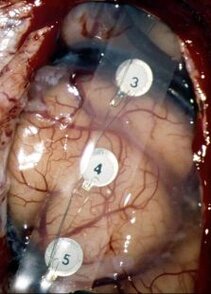

Elektrophysiologische Stimulation (ES)

Mit der elektrophysiologischen Stimulation können bei einem neurochirugischen Eingriff am Hirntumor einzelne Gehirnfunktionen stimuliert und damit vorübergehend aktiviert oder deaktiviert werden. Dies ist besonders hilfreich, um kritische Hirnareale, v. a. die Motorikregion, zu entdecken und bei der Operation schonen zu können.